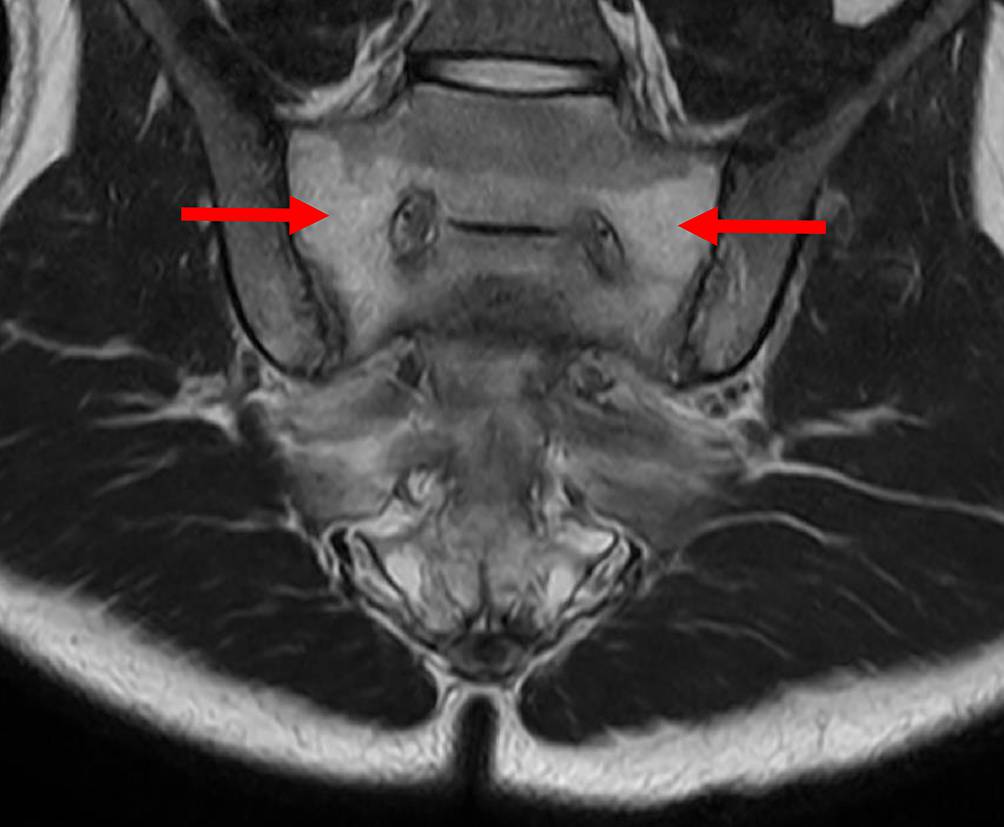

Das KM-Ödem allein ist ein bildgebender Befund, der erst zusammen mit klinischen Symptomen und Befunden als KM-Ödemsyndrom oder Erkrankung angesehen wird [19]. Mit Gelenksschmerz, aber ohne zugrunde liegende Pathologie oder Erkrankung wird es als primäres KM-Ödemsyndrom betrachtet [20], das sekundäre KM-Ödemsyndrom gilt nicht als unabhängige Diagnose. Es tritt dann beispielsweise im Rahmen von Arthrose, Spondyloarthritis (siehe Beispiel in Abb. 1) oder rheumatoider Arthritis, Infektion oder Trauma (siehe Beispiel in Abb. 2) auf [21]. Bis heute gibt es aber zu dieser Unterscheidung keinen internationalen Konsens in der Literatur, mit klarer Definition und Validierung für alle beteiligten Fachdisziplinen.

Abb. 1

Subchondrales Knochenmarködem bei Sakroiliitis re im Rahmen einer axialen Spondyloarthritis (T2-gewichtete Aufnahme). Die entzündlichen Lumbiosakralgien zeigten ein Ansprechen auf nicht-steroidale Antirheumatika